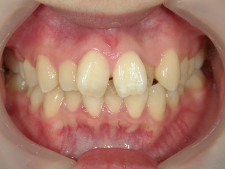

矯正歯科 治療前矯正歯科 治療前

矯正歯科 治療前

no.8_8495_治療前_左.jpgno.8_8495_治療前_正面.jpgno.8_8495_治療前_右.jpg